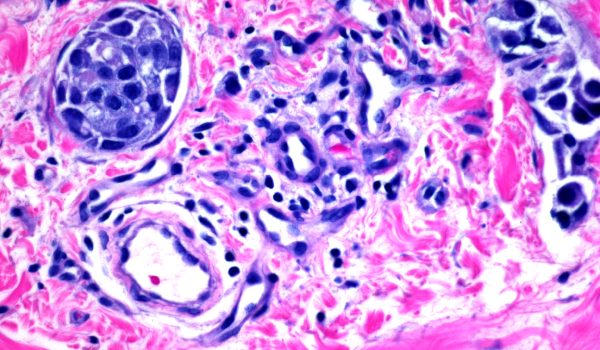

در سرطان التهابی پستان سلول های سرطانی وارد عروق لنفاوی داخل پستان میشوند و این عروق را مسدود می کنند. این انسداد باعث تورم پستان و پوست آن میشود زیرا مایع لنفاوی نمیتواند خارج شود. همچنین این اتفاق میتواند باعث شود پستان قرمز و ملتهب به نظر برسد .